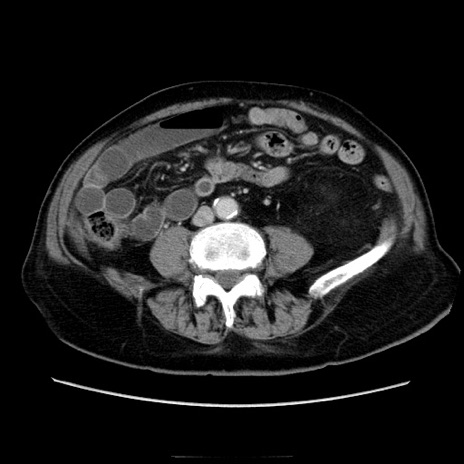

症例21(横断像)

【症例】70歳代男性

【主訴】腹痛

【現病歴】肝硬変・肝細胞癌にてかかりつけの方。約9時間前に食後より腹痛出現。症状が徐々に増悪し、嘔吐出現したため来院。

【既往歴】肝硬変、肝細胞癌(RFA、TACE後)

【身体所見】意識清明、表情苦悶様、BT 36℃、BP 129/78mmHg、P 88bpm、SpO2 97%(RA)、右上腹部から心窩部にかけて圧痛あり、反跳痛なし、筋性防御あり。

【データ】WBC 5800、CRP 0.16